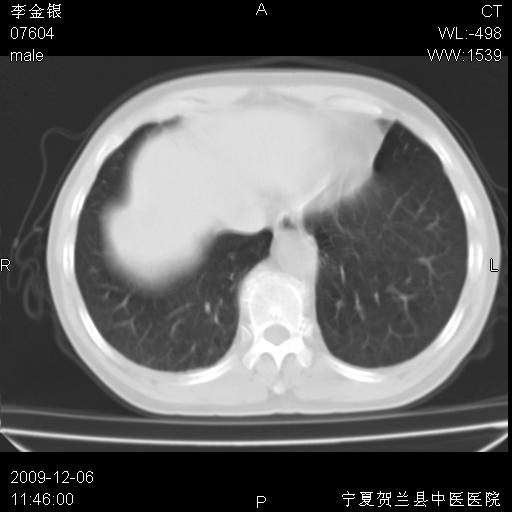

该病人 ,男,62岁,主因咳痰带血两天

考虑右肺中央型占位性病变并阻塞性肺炎.(右肺上叶支气管变窄),建议支纤镜检查.

考虑右肺中心型肺癌伴阻塞性肺炎及右肺门淋巴结转移,建议纤维支气管镜进一步检查。

支气管壁明显增厚 管腔狭窄,腔静脉后多个淋巴肿大,结合年龄病史考虑右肺上叶中央型肺癌并阻塞性肺炎

右肺上叶后段支气管阻塞,右上肺门占位,相应肺段阻塞性肺炎,右肺门有淋巴结肿大。诊断右肺上叶中心型肺癌,阻塞性肺肺炎、右肺门淋巴结转移。

右上叶支气管狭窄,管壁增厚,远端斑片状软组织影,病灶邻近叶间裂,叶间裂无移位。

诊断右肺中央型肺癌。

那个片影应该大部分都是病灶,病灶沿肺段支气管分支生长,后段完全显示不清、闭塞。若为不张应该伴有叶裂的移位,若为炎症应有空气支气管征。

右肺中心型肺癌伴阻塞性肺炎及右肺门与纵膈淋巴结转移很典型,可纤维支气管镜进一步检查

考虑右侧中央型肺癌伴右肺上叶后段阻塞性炎症、肺不张、右肺门和纵隔淋巴结肿大。

右肺上叶中心型肺癌,阻塞性肺炎、右肺门和纵隔淋巴结转移。